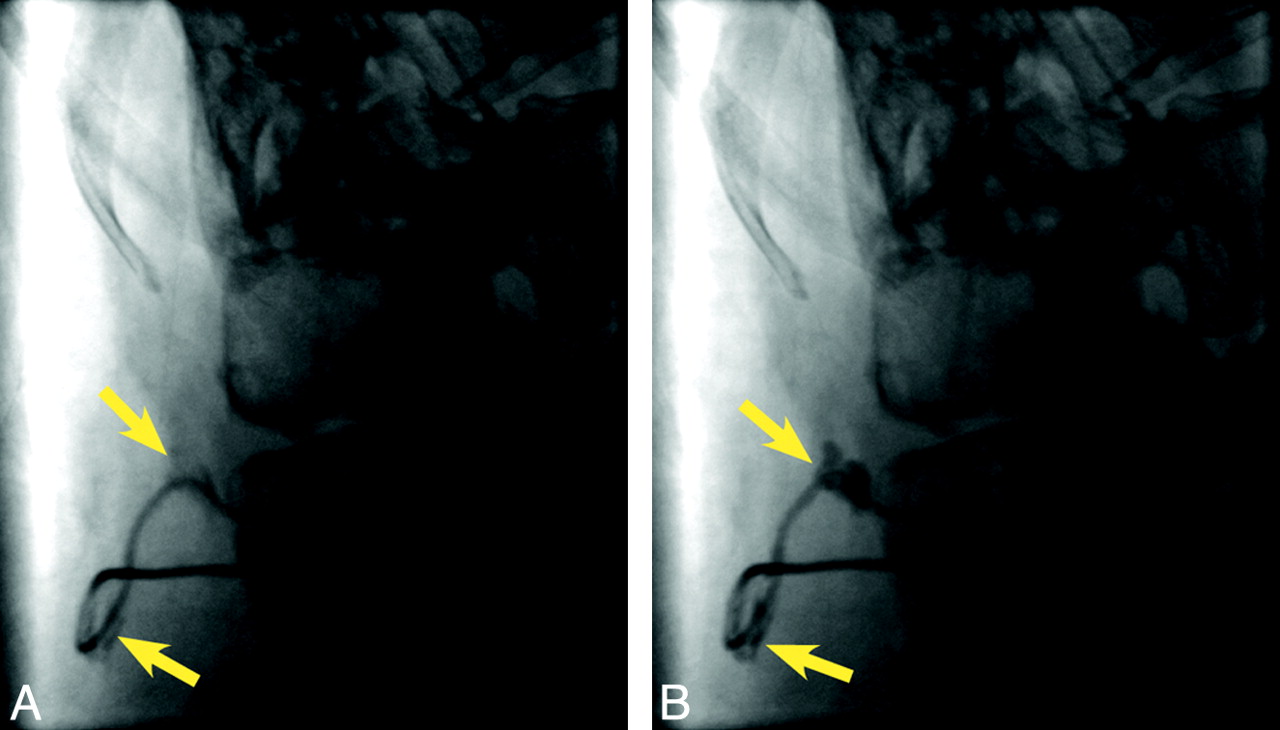

Fluoroscopic studies are the next step if plain films are not diagnostic. As mentioned above, 2–3 mL of fluid should first be aspirated from the accessory port to avoid rapidly delivering the residual catheter baclofen to the patient during contrast injection, which can cause a life-threatening baclofen overdose.39 If CSF is successfully aspirated and the patient's symptoms are relatively mild, programming an intrathecal baclofen bolus through the pump-catheter system as a therapeutic trial is reasonable.34 If the patient's symptoms are severe or there is no response to a baclofen bolus, fluoroscopy during contrast injection through the accessory port is indicated. Disconnection of the catheter from the pump (Fig 6), macroscopic perforations (Fig 7) and leaks (Fig 8), as well as catheter-tip dislodgments or migration can sometimes be visualized during such injection studies when plain films are unrevealing. Viewing the injected catheter under fluoroscopy during positional changes of the patient can also be beneficial if there is any historical suggestion that symptoms are position-dependent (ie, spasticity is more pronounced when the patient has been supine for a prolonged period of time, etc).

Lateral fluoroscopic spot image (A) reveals extravasating contrast (yellow arrows) from an apparently intact catheter. Further extravasation (arrows) is demonstrated during continued injection (B), consistent with catheter perforation.